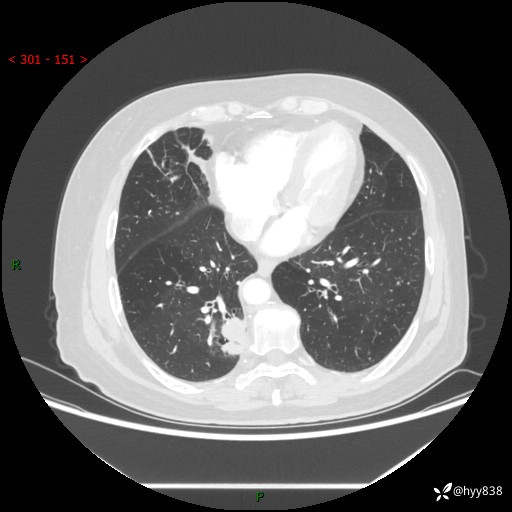

胸部CT肺窗(平扫外院)